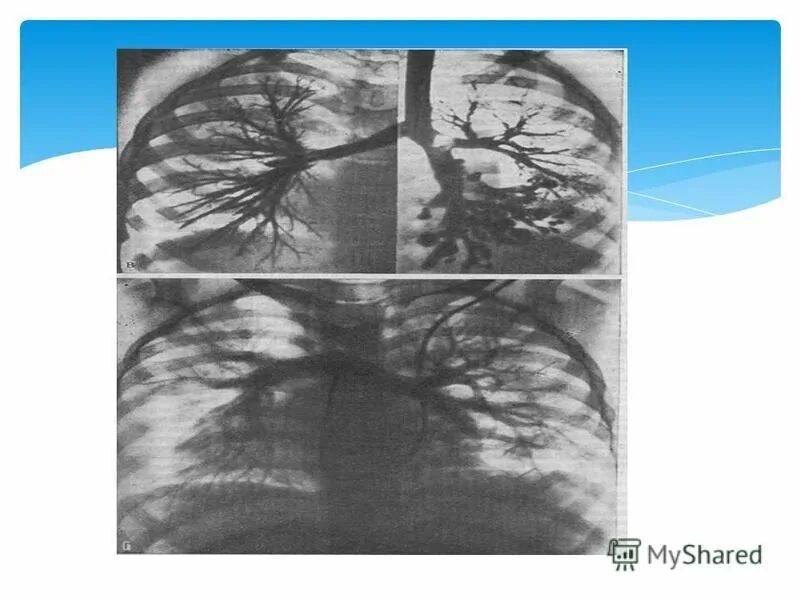

Аномалии органов дыхания